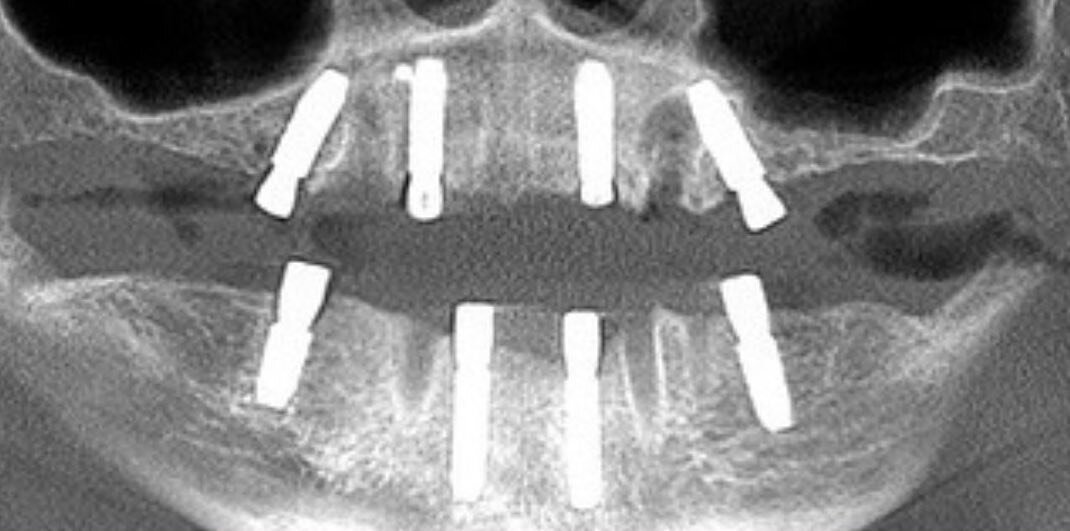

Установлено по 4 имплантата на каждую челюсть.

Основа протеза - титановая балка, долговечная и надежная конструкция. На эту балку устанавливается условно-съемный протез с искусственными зубами.

Протез очень комфортный: он не перекрывает небную поверхность и не требует длительного привыкания.